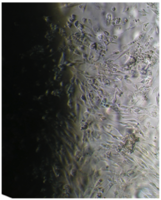

Культуру дермальных фибробластов получали из кожно-мышечной ткани, а культуру мезенхимальных стромальных клеток – из фрагментов крыши черепа абортусов сроком 6-10 недель методом первичных эксплантатов (рис. 1, 2).

Образец исследуемого материала - кусочек недеминерализованной спонгиозы серии «Лиопласт»® объемом 125 куб. мм (рис. 31) помещали на равномерный монослой фибробластов плотностью 332 клетки/ммІ.

Рис. 31. Недеминерализованная спонгиоза серии «Лиопласт»®.

Через сутки монослой как в контроле, так и в опыте был целостным и равномерным, фибробласты сохраняли обычную форму и размеры.

Вид монослоя и структура клеток не отличались от обычных в течение всех четырех суток наблюдения (рис. 32).